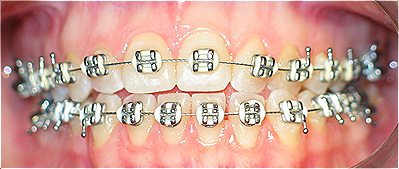

Apinhamento dentário com os dentes caninos em desoclusão (classe II, divisão 2).

![]() |

Após dois anos de tratamento ortodôntico.